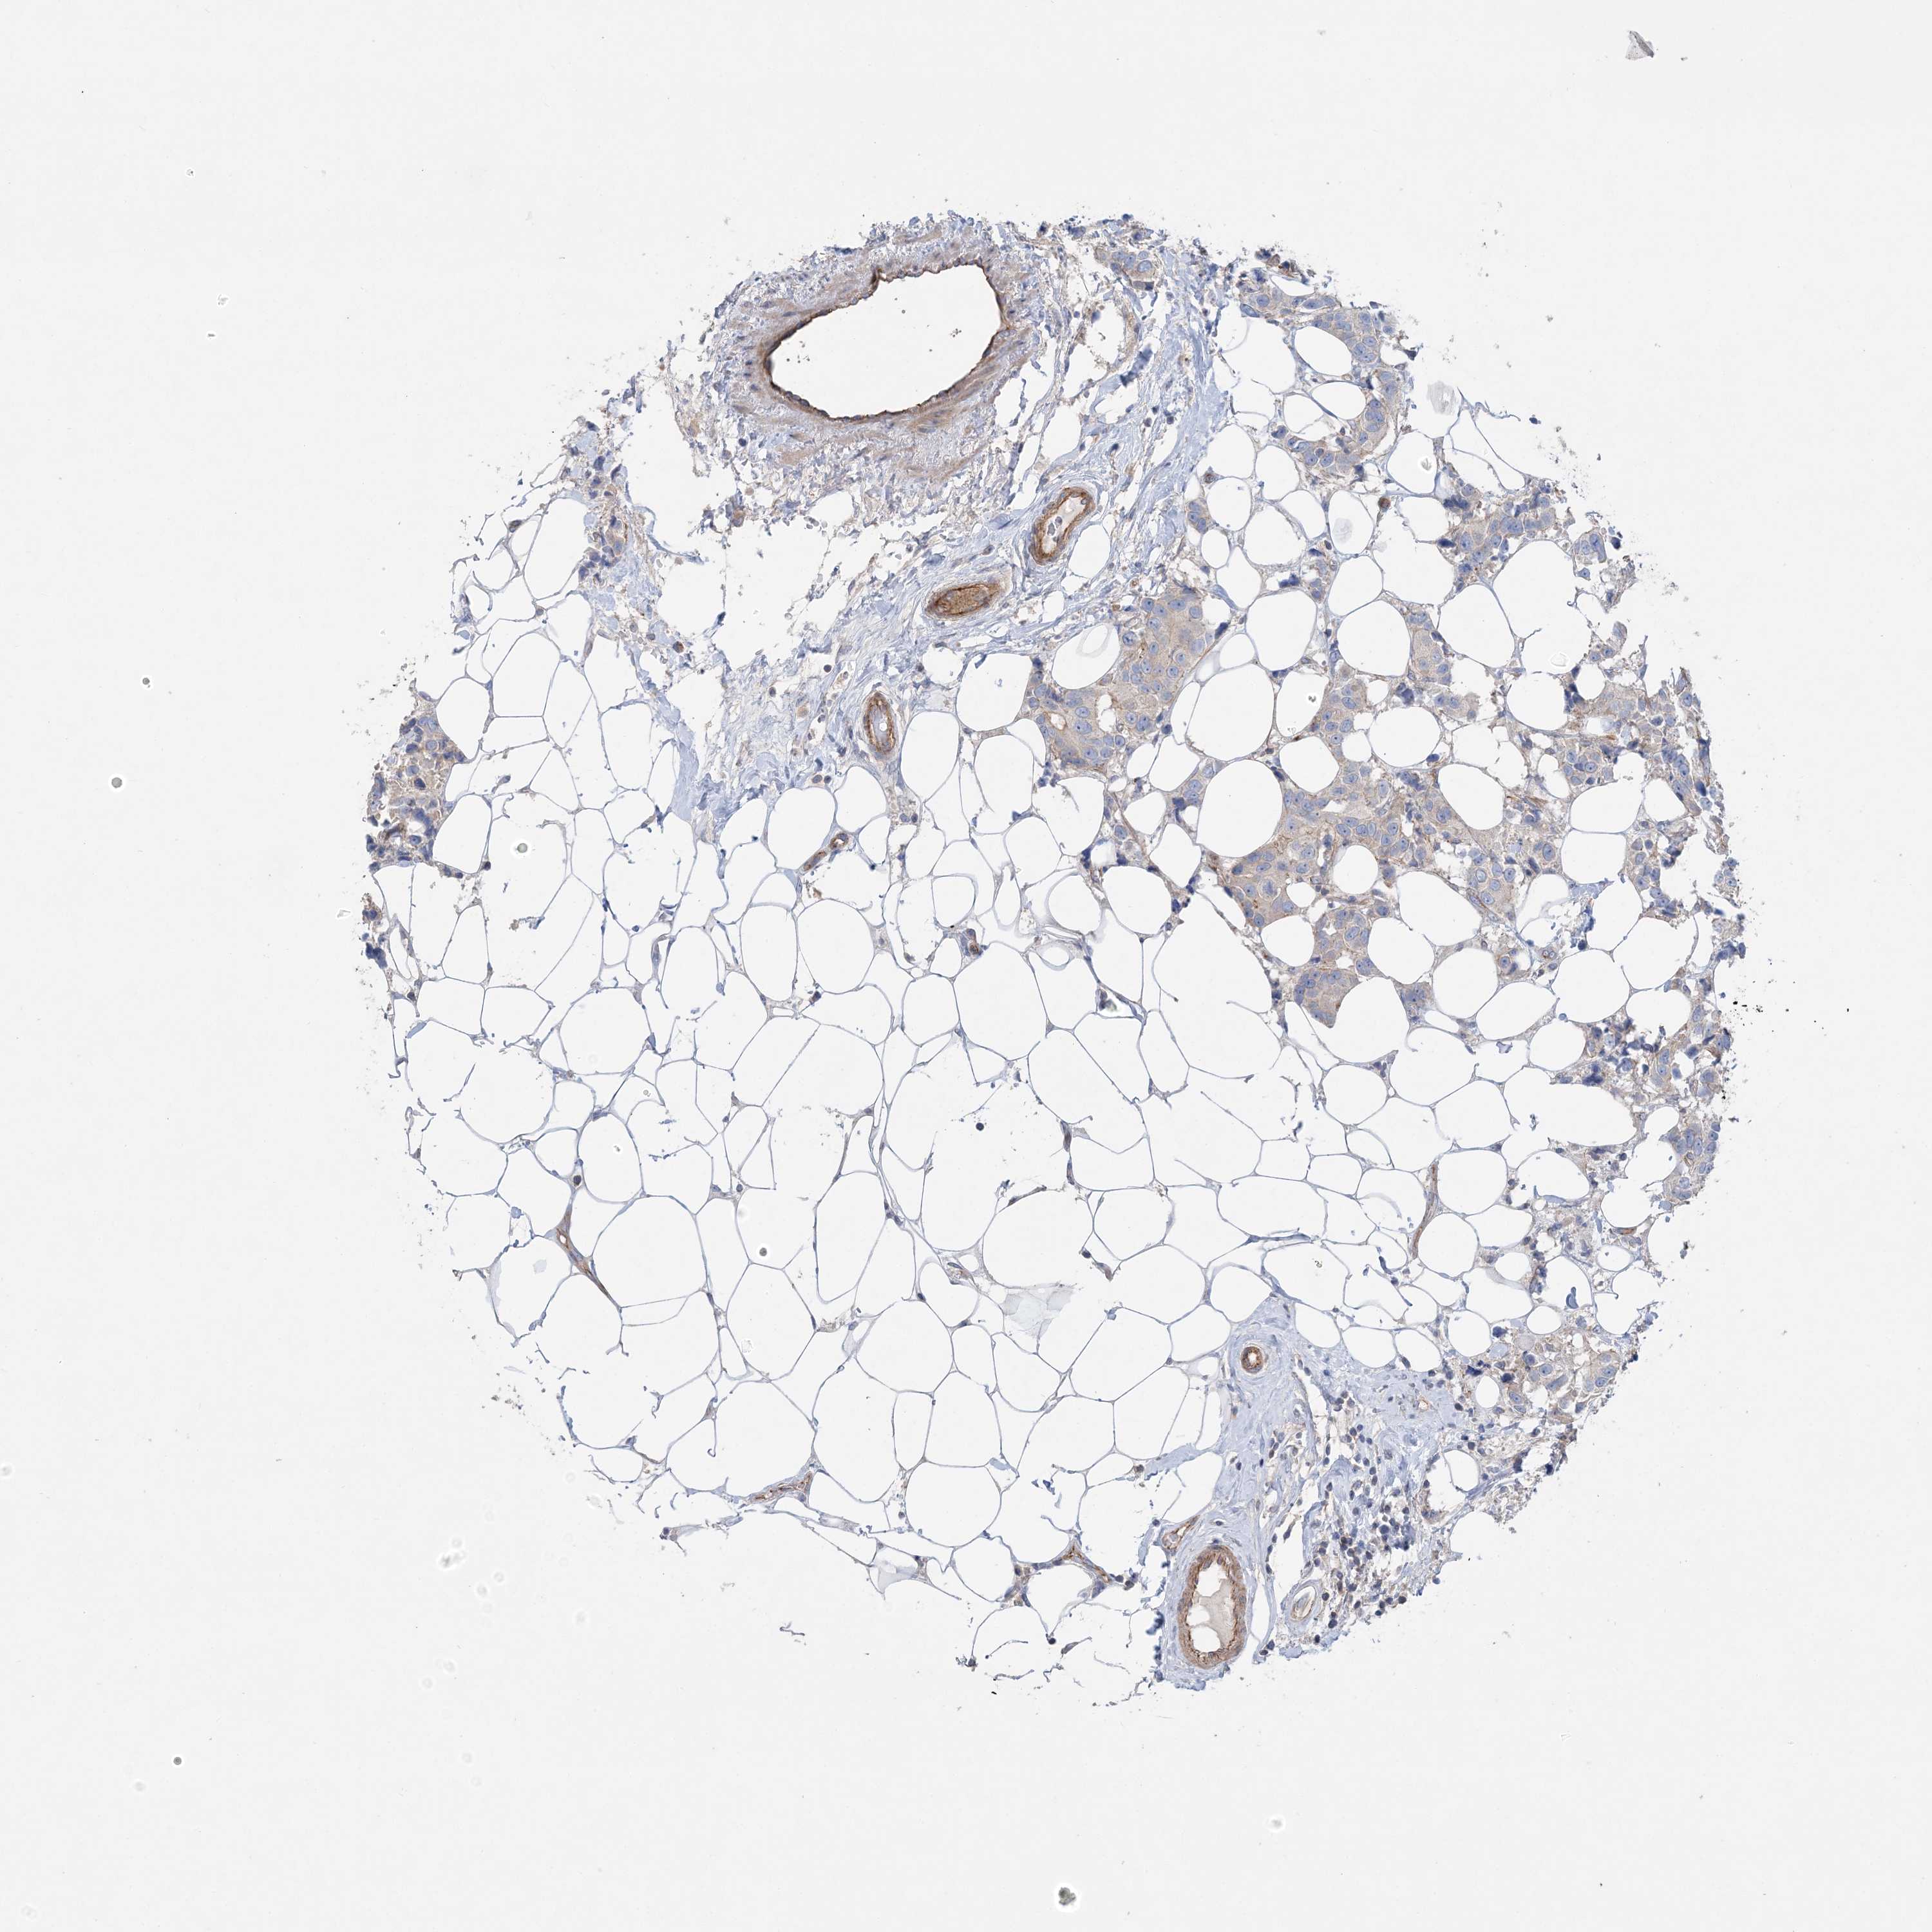

CANCER BREAST CANCER Show tissue menu

BRCA TCGA BRCA VALIDATION PROTEIN EXPRESSION